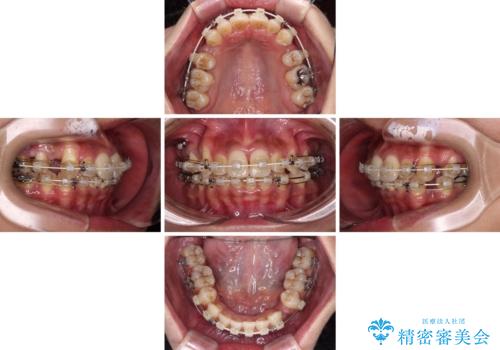

- 八重歯と上下前歯のでこぼこを気にして来院された患者様です。

上下前歯部叢生のスペース獲得のため、上下顎左右小臼歯各1歯(計4本)を抜歯して、ワイヤー装置にて矯正治療を行うこととしました。

上下の正中位置が大きくずれていたため、上下正中が合わないまま終了することが予想されましたが、思っていた以上にスムーズに歯が移動し、満足いただける仕上がりとなりました。